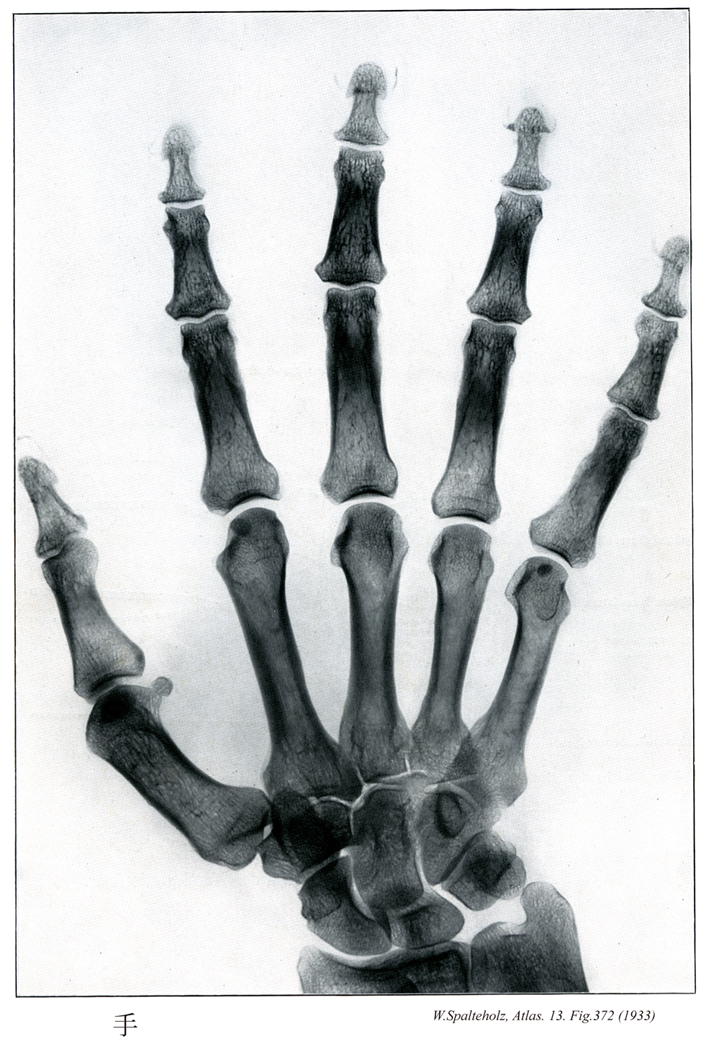

372

【Hand

手;テ

Manus】

→(手は上肢のうち橈骨手根関節より遠位の部分。手根と中手に区別され、手根と中手の前面を手掌、後面を手背という。皮膚節において第六頚神経、第七頚神経、第八頚神経のレベル。)